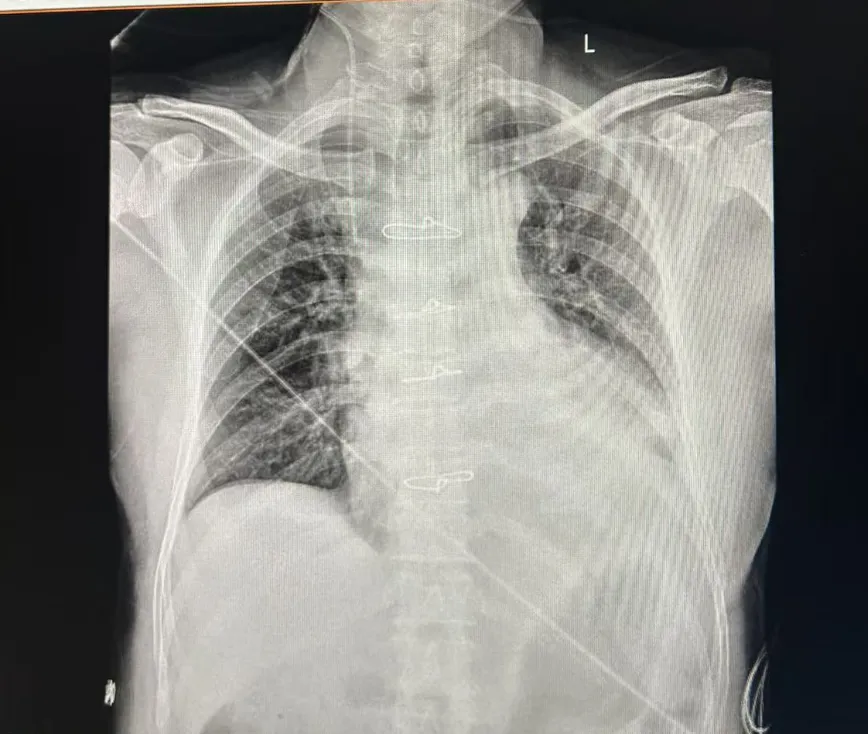

术后CT

患者升主动脉增宽,主动脉瓣二瓣化畸形,瓣膜可见重度狭窄并关闭不全,经团队术前全面评估,决定为其行主动脉瓣生物瓣置换术,术中顺利植入25# 美敦力Avalus零金属生物瓣,精细完成人工血管置换,取得了理想的治疗效果。患者术后恢复顺利,复查显示Avalus生物瓣功能良好,血流动力学稳定,吻合口无出血及相关并发症。此次手术的成功,不仅验证了南昌大学第一附属医院团队在高难度主动脉手术中的高超技术,更为同类复杂心脏手术患者的手术全生命周期管理提供了重要参考。